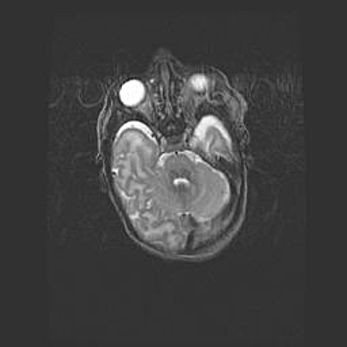

Мальформация Денди-Уокера. Киста задней черепной ямки.

Агенезия мозолистого тела.

Возраст: 2,5 месяца

Вес: 2420 г

Пол: женский

Окружность головы: 37 см

Срок гестации: 32 недели

Мальформация Денди—Уокера — редкий вид патологии ЦНС, представляющий собой врожденный порок развития каудального отдела ствола и червя мозжечка, ведущий к неполному раскрытию срединной (Мажанди) и латеральных (Лушка) апертур IV желудочка мозга. Для этогно синдрома характерна триада симптомов: гипотрофия червя мозжечка и/или полушарий мозжечка, кисты задней черепной ямки, гидроцефалия различной степени. В 70% случаев порок сочетается и с другими аномалиями головного мозга, в частности с агенезией мозолистого тела.